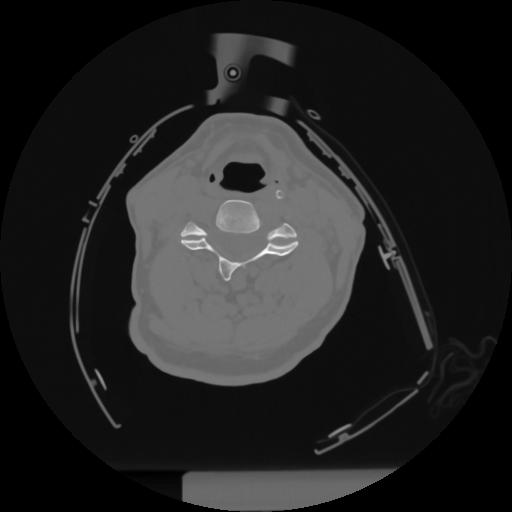

12 P.BLANDAS,,Vol,0.5,P.BLANDAS,,